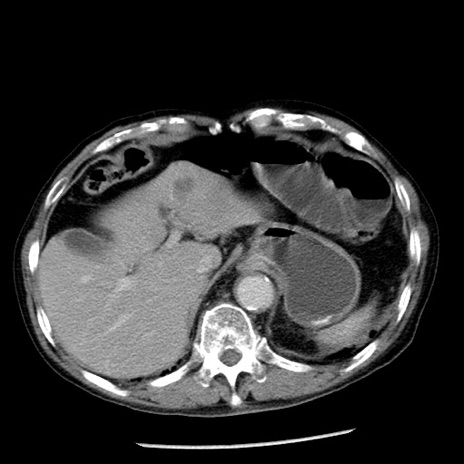

冠状断像

症例26(横断像)

【症例】80歳代男性

【主訴】嘔吐

【現病歴】昨晩2回嘔吐あり、今朝になっても嘔吐あり。来院。

【既往歴】胃潰瘍

【身体所見】意識清明、BT 37.6℃、BP 166/95mmHg、HR 100bpm、SpO2 97%、腹部:平坦・軟、腸蠕動音聴取良好、圧痛なし。

【データ】WBC 21900、CRP 1.46